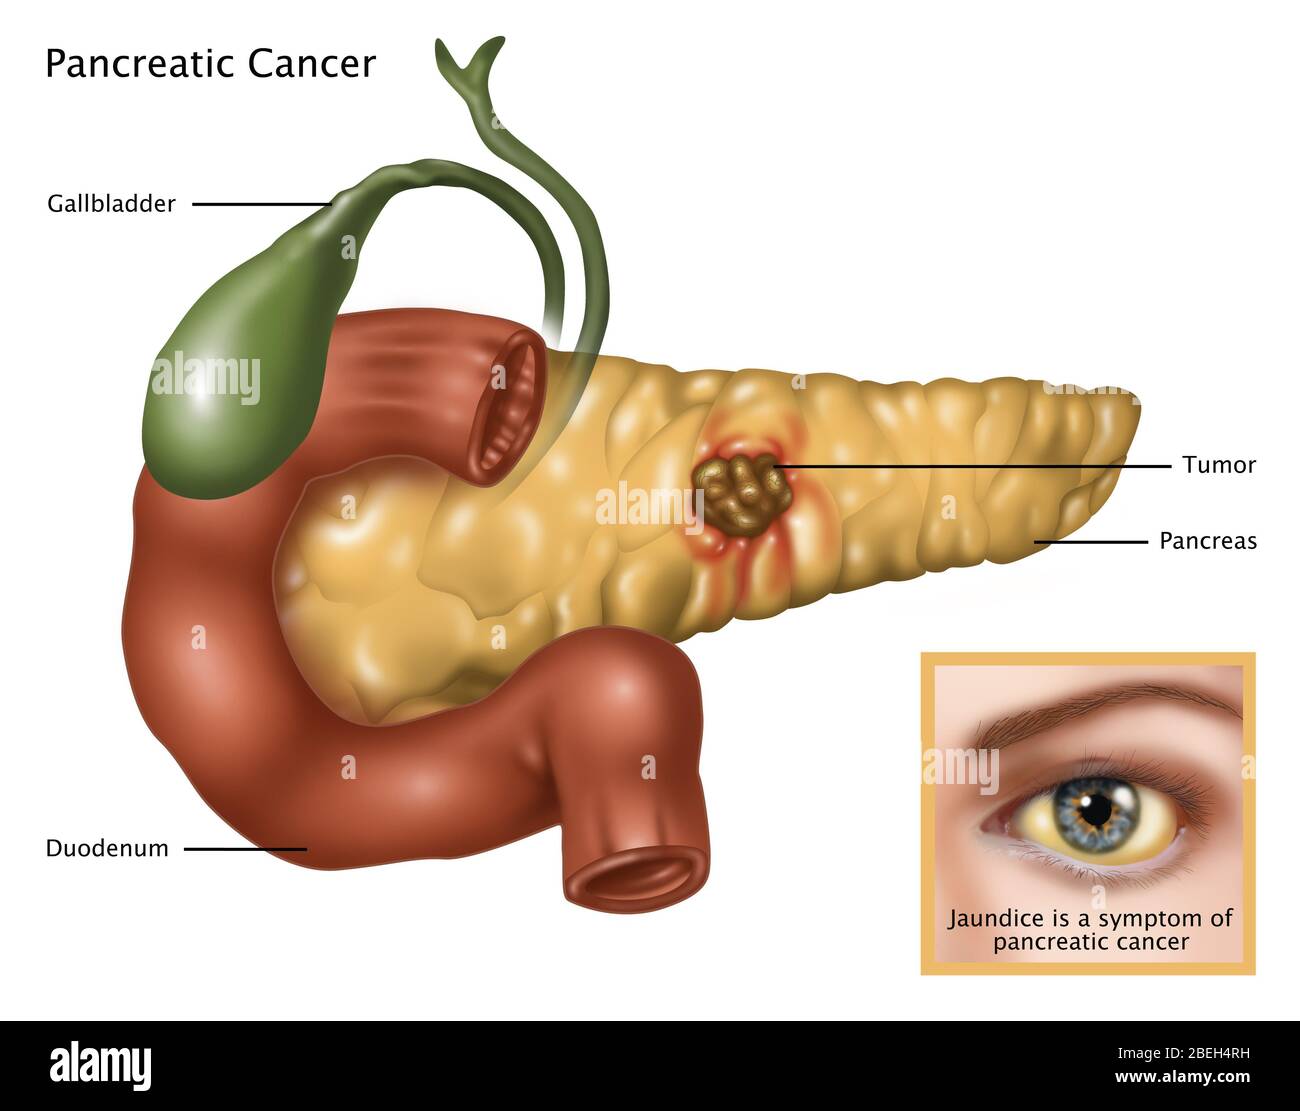

La jaunisse, ou ictère, est un signe clinique important. Elle se caractérise par une coloration jaune de la peau et du blanc des yeux. Cette coloration est due à une accumulation de bilirubine dans le sang.

La bilirubine est un pigment jaune produit lors de la dégradation des globules rouges. Normalement, la vésicule biliaire et le foie contribuent à son élimination. Une obstruction des voies biliaires, causée par une tumeur, empêche cette élimination.

L'apparition d'une jaunisse est un signe d'alerte majeur. Elle nécessite une consultation médicale rapide. Elle peut être associée à des urines foncées (bilirubinurie) et à des selles décolorées (acholie).